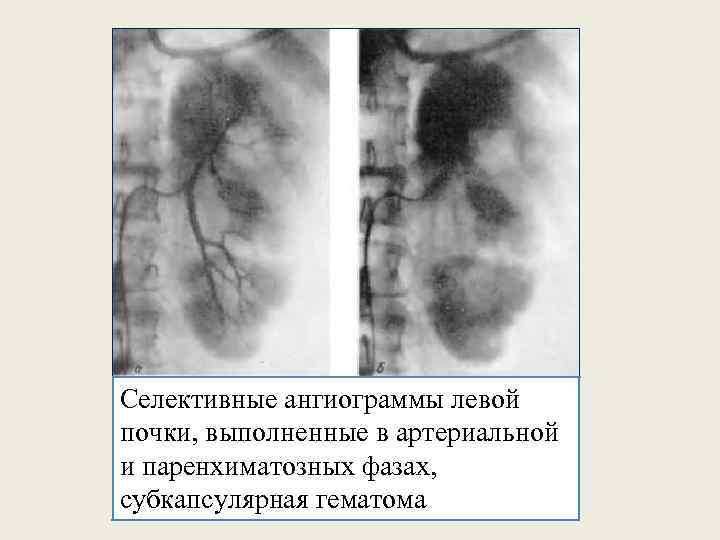

Селективные ангиограммы левой почки, выполненные в артериальной и паренхиматозных фазах, субкапсулярная гематома